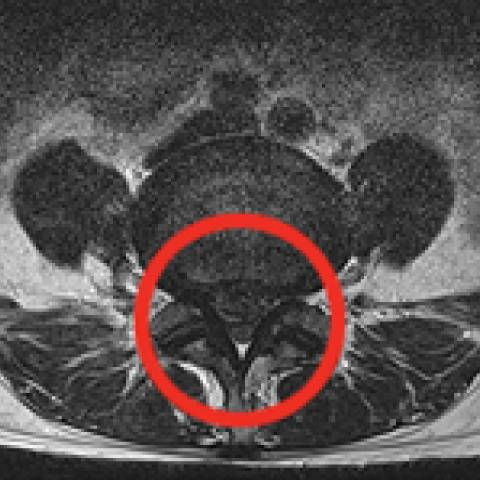

터진 디스크를 내시경으로 제거하는 모습